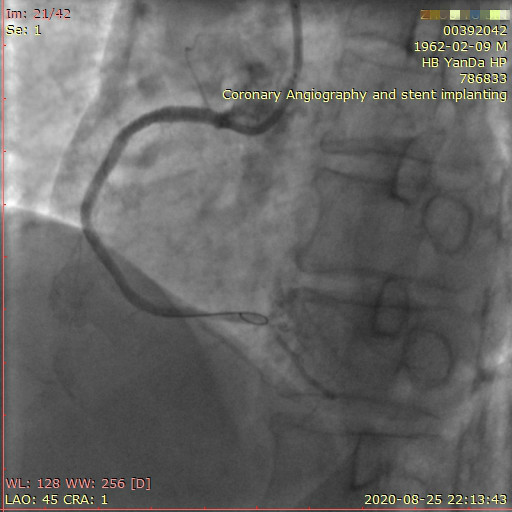

李先生右冠術前影像

李先生右冠術后影像

術前,翟光耀主任還親自為李先生復查冠狀動脈造影,造影結果顯示:患者的前降支、回旋支、右冠等冠脈三支嚴重病變、嚴重鈣化,且均為彌漫性長病變,最重處99%以上管腔極嚴重狹窄。翟主任仔細閱讀造影結果后指出:結合李先生的實際情況,雖然微創介入手術難度比較大,但仍可行;李先生心臟三支主干動脈均存在極其嚴重的狹窄,每一支動脈均至少植入2-3枚支架,根據患者的耐受情況,李先生可能需要分3次分別對三支動脈進行介入手術;考慮到李先生路途遙遠,病情嚴重,不宜反復奔波,并且患者迫切要求能夠徹 底解決病痛,在病情允許的情況下,如果手術順利,爭取為患者進行“一站式”手術,一 次 性解決全部三支動脈病變!

李先生足位術前影像

李先生足位術后影像

手術方案確定之后,在心血管內三科趙景新主任、介入醫學科富孝晨主任的配合下,翟光耀主任親自擔任主刀,分別依次對李先生的三支動脈進行了完全血運重建。由于手術進展順利,李先生術中沒有任何癥狀,耐受良好,于是成功的將三支動脈“一站式”治療!術中,由于李先生左主干遠端分叉處存在嚴重病變,翟光耀主任選擇國際指南推薦的DK-mini-Crush技術,確保了分叉處兩支主干開口均萬無一失。據悉,DK-mini-Crush技術是目前冠脈分叉病變領域最為復雜及難以掌握的介入技術之一,對手術醫生經驗、體力均提出了極大的挑戰。極為擅長復雜介入技術的翟光耀主任卻用嫻熟的技術確保了李先生手術的成功。

冠狀動脈嚴重鈣化合并狹窄病變是冠脈介入的一大難題,血運重建難度大,成功率低,并發癥發生率高,該例患者的成功救治標志著我院冠脈介入水平又躍上了一個新的臺階。